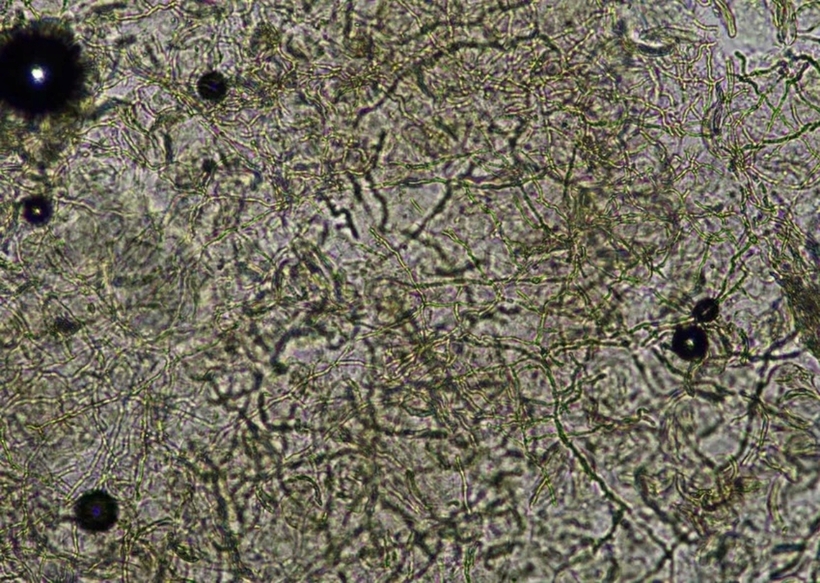

Vài tuần sau tái lại, ngứa nhiều hơn và lan rộng xuống mông, đùi, lên tay, nách, lưng… Qua thăm khám lâm sàng, bác sĩ chỉ định làm một số xét nghiệm như soi tươi tìm sợi nấm có phát hiện các sợi nấm chia đốt trên nền tế bào sừng.

Bệnh nhân được chẩn đoán nhiễm nấm da toàn thân và được kê đơn thuốc điều trị tại nhà, hướng dẫn chế độ sinh hoạt, vệ sinh phù hợp để hạn chế tái phát.

Hình ảnh nấm sợi dưới kính hiển vi. Ảnh: Pháp Luật TP.HCM

Bà Phạm Thị Thu Giang, CKI xét nghiệm, Viện Sốt rét – Ký sinh trùng – Côn trùng TP.HCM khuyến cáo người dân cần chú ý giữ quần áo, giày dép khô ráo, thoáng mát. Sau khi lội nước, gặp mưa ướt cần vệ sinh tay chân với xà phòng và nước sạch, lau khô.

Khi phát hiện vùng da bị ngứa và xuất hiện các chấm đỏ lây lan hình vòng cung, cần đến cơ sở y tế chuyên khoa khám, xét nghiệm để có thuốc uống, bôi phù hợp, tránh để lây lan sang vùng da khác trên cơ thể.

“Việc sử dụng thuốc điều trị không đúng cách có thể khiến tình trạng bệnh trở nên nghiêm trọng hơn và cần thời gian điều trị kéo dài hơn”, bà Giang nói.